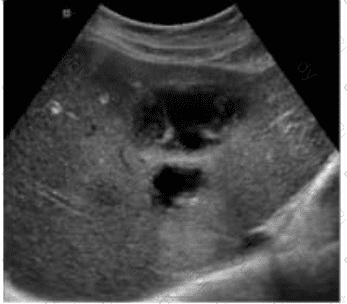

Which abnormality is depicted in this image of a patient who presents with a fever following a liver biopsy?